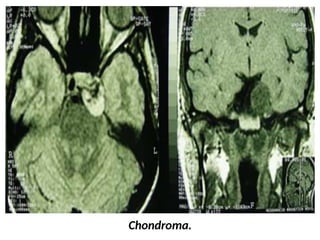

Chordoma and Chondrosarcoma

Chondromatous tumors develop from embryonic cartilaginous remnants

enclosed in the bones of the skull base.

They often arise from the petrooccipital or sphenooccipital

synchondrosis and destroy the adjacent bones.

Chondromatous tumors can be hypoattenuating at CT, possibly with a

marginal high- attenuation area due to a dense matrix of hyaline

cartilage or massive calcification. Lytic bone erosion may be seen.

At MR imaging, the tumor is hypointense on T1- weighted images and

heterogeneously hyperintense on T2-weighted images; it enhances

poorly due to its hypovascularity.

Chondroma.

Chordoma and Chondrosarcoma Chondromatoustumors develop from embryonic cartilaginous remnants enclosed in the bones of the skull base. They often arise from the petrooccipital or sphenooccipital synchondrosis and destroy the adjacent bones. Chondromatous tumors can be hypoattenuating at CT, possibly with a marginal high- attenuation area due to a dense matrix of hyaline cartilage or massive calcification. Lytic bone erosion may be seen. At MR imaging, the tumor is hypointense on T1- weighted images and heterogeneously hyperintense on T2-weighted images; it enhances poorly due to its hypovascularity.

• #41 Chondrosarcoma: large mass localized on the right petroclival fissure invading the right cavernous sinus and extending to the posterior fossa with mass effect on the pons. CT shows stippled calcifications and petrous apex erosion (a). This mass is strongly hyperintense on T2-wi (b), and shows heterogeneous enhancement after contrast (c).

• #42 Chordoma: mass centered on the clivus and the right cavernous sinus, heterogeneously hyperintense on T2-wi. (a), hypo- to isointense on T1-wi with an heterogeneous enhancement after contrast (b) corresponding to a chordoma.